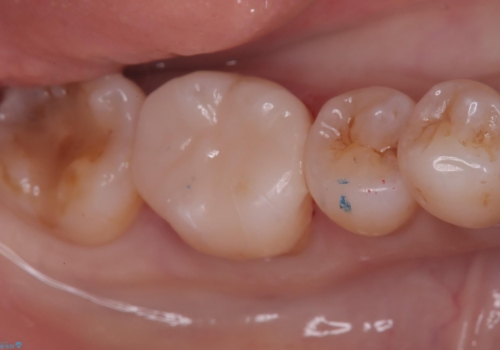

銀歯の周りから進行したむし歯 欠けてしまった歯をオールセラミッククラウンに